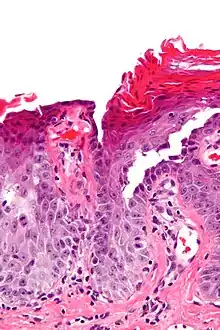

| Micrograph of transient acantholytic dermatosis, showing subcorneal separation and acantholysis. H&E stain. | |

Grover's disease (GD) is a polymorphic, pruritic, papulovesicular dermatosis characterized histologically by acantholysis[2]: 529 with or without dyskeratosis.[3] Once confirmed, most cases of Grover's disease last six to twelve months, which is why it was originally called "transient". However it may last much longer. Nevertheless, it is not to be confused with relapsing linear acantholytic dermatosis.

Grover's may be suspected by its appearance, but since it has such a characteristic appearance under the microscope a shave skin or punch biopsy is often performed.